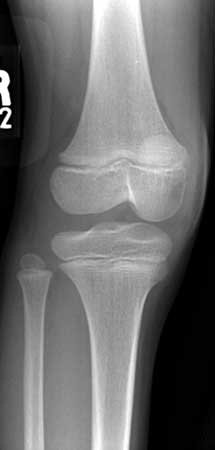

Una rodilla normal en persona de 12 años (vista oblicua).

Nota: Las imágenes se muestra para fines ilustrativos. No trate de sacar conclusiones comparando esta imagen con otras en el sitio. Solamente los radiólogos calificados deben interpretar las imágenes.